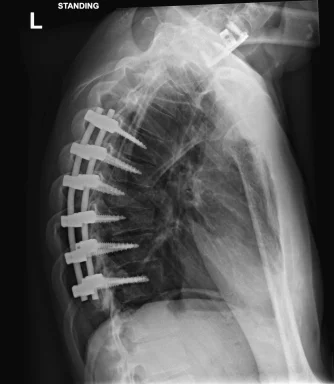

My TRT journey started in June 2020 when i crashed my motorcycle on a UK race track in the wet at 80-90mph into an earth embankment tyre wall (ouch !). Very lucky to be still here, and the list is way too long of all my physical injuries, but included multiple fractures etc with worst being broken neck & my spine in 7 places. Got some awesome Xrays lol (attached!). I can walk (slowly) & talk so i aint complaining